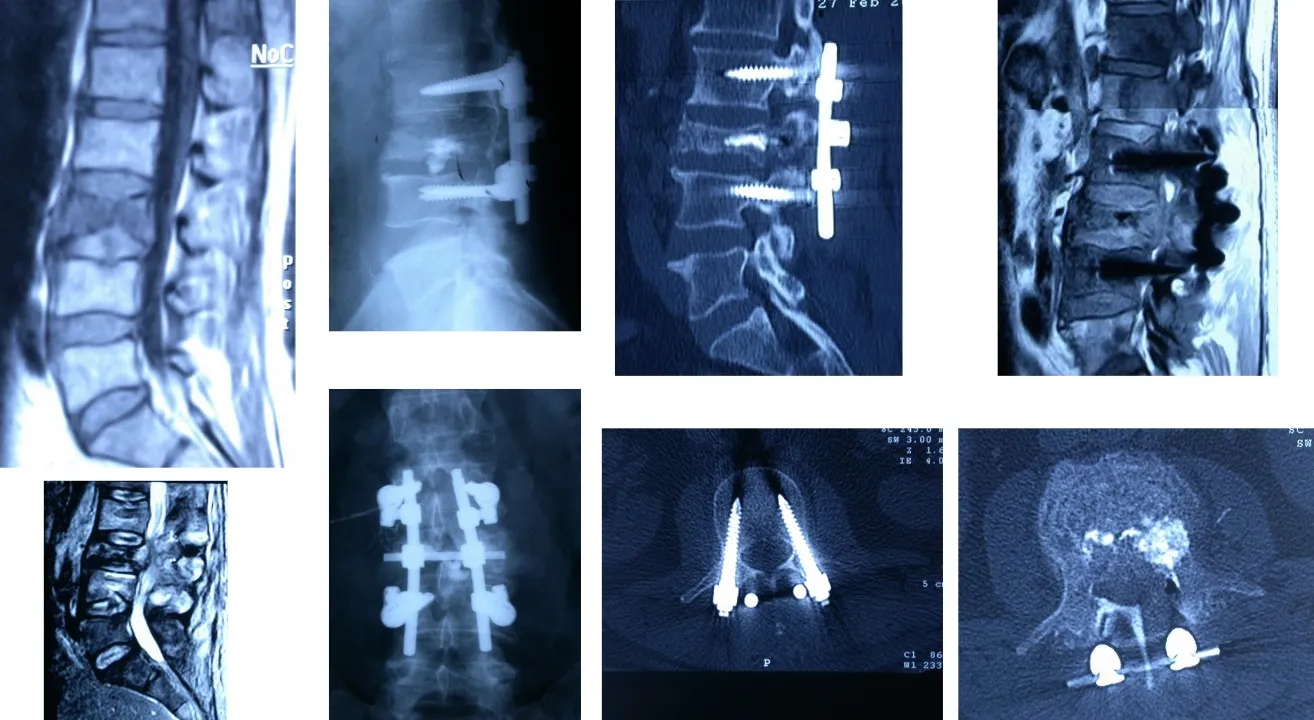

El diagnóstico se apoya en estudios de imagen, siendo la resonancia magnética (RM) la técnica fundamental para valorar la extensión tumoral y su relación con la médula espinal. La tomografía axial computarizada (TAC) permite definir con precisión la afectación ósea y planificar el abordaje quirúrgico. En ocasiones, se requiere una biopsia para determinar la naturaleza histológica del tumor y orientar el tratamiento.

El tratamiento depende del tipo de lesión, su extensión y el estado del paciente. En casos metastásicos, el objetivo principal es paliar el dolor y preservar la función neurológica, combinando cirugía descompresiva, estabilización mediante instrumentación vertebral y tratamientos adyuvantes como radioterapia o quimioterapia. En los tumores primarios, especialmente los benignos o de bajo grado, se intenta la resección completa, recurriendo a técnicas de cirugía mínimamente invasiva y neuronavegación 3D, que aumentan la precisión y reducen las complicaciones..

Los avances tecnológicos han permitido desarrollar abordajes quirúrgicos desde cualquier ángulo de la columna (anterior, posterior, lateral), con equipamiento sofisticado como neuronavegadores 3D, neurofisiología intraoperatoria y técnicas de fijación avanzadas, lo que ha reducido significativamente los riesgos quirúrgicos.

La técnica neuroquirúrgica ha avanzado de forma notable en los últimos años, hasta el punto de que hoy es posible abordar toda la columna vertebral, desde la base del cráneo (a través de la boca) hasta el sacro, mediante vías anterior, posterior o lateral, según la localización y la naturaleza del tumor. En la actualidad, prácticamente no existe ninguna zona de la columna que no pueda abordarse quirúrgicamente con seguridad y precisión, gracias a estos progresos técnicos y tecnológicos.

Otra opción es acceder por vía posterior, lo que permite realizar una fijación más sólida y estable mediante la colocación de tornillos y barras en los elementos posteriores de la columna. Este tipo de abordaje ofrece un mayor refuerzo estructural, especialmente útil cuando existe pérdida de sostén anterior o es necesario complementar una reconstrucción realizada previamente por vía anterior.

También es posible realizar el abordaje por vía posterior, a través del cual se pueden efectuar tanto la resección de los tumores como la colocación de los sistemas de fijación necesarios para estabilizar la columna, tal como se observa en la figura. Este abordaje permite al cirujano acceder directamente a las estructuras posteriores vertebrales y realizar una descompresión neurológica precisa cuando existe afectación del canal raquídeo.